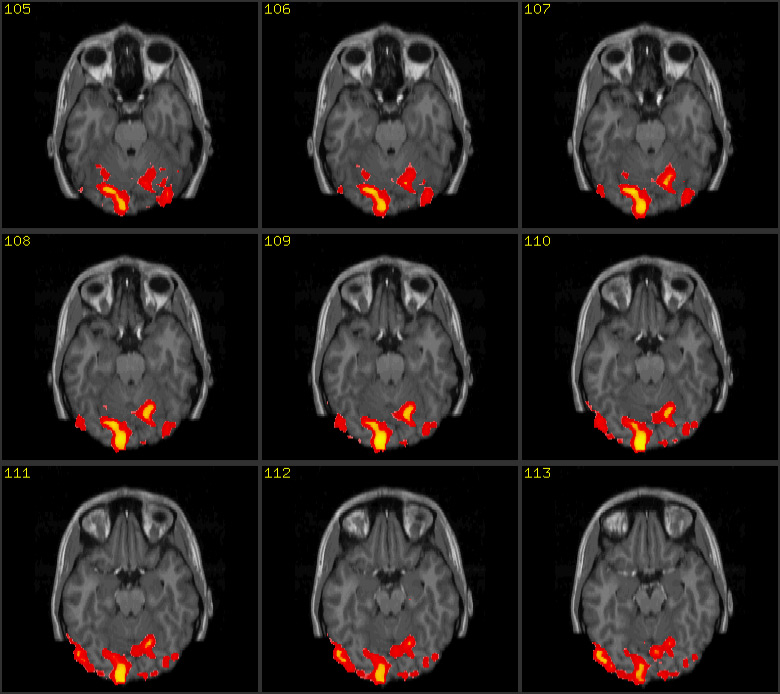

The automatism and, at the same time,

ineffability of thinking can be put into an image thanks to progresses in

neuroscience and biomedical techniques of image formation and visualization.

The illustration shows two images: the first one is a scan of the brain

obtained with Magnetic Resonance Imaging (MRI), the second is its functional

version (fMRI). MRI is a non-invasive scientific technique that generates

images of the body for diagnostic and research purposes. Along with its

functional version, MRI has been extensively applied to studies of brain

anatomy and cognitive functions, enabling researchers to detect and measure

the neuronal activity in almost real time. By showing the human brain at work,

brain scans are presented in the wider public arena and, specially, in the

media, as evidence of conditions of normality or illness that prompt us to

reshape our concept of personal identity (Dumit 2004).14

Brain scans embody both image traditions

that historian of science Peter Galison individuated within the field of

physics: the first tradition, called logical, substitutes the notion of the

image with the notion of statistical projection of data and digital

information; the second tradition, called image, describes images as natural,

illusionary or mimetic. According to this second tradition, images ‘preserve the form of things as

they occur in the world’ (Galison, 1997, 807). Brain scans function as authoritative

visual objects that are part of a multi-layered ensemble of networked

techniques and technologies (both analogical and digital) and human mediations,

embodying the logic of the database (de Rijcke and Beaulieu, 2014) and being

more the statistical projections of data rather than representations.

Therefore, brain scans can be aptly called image-data.

Experts in the laboratory do not always need to see the image because they are capable of reading it in accordance with the aforementioned logical tradition. Non-experts, on the contrary, can interpret the brain scan only as an image belonging to the second tradition. Both strategies, reading and seeing, however, are made possible thanks to notions that belong to art history and practice such as perspective, background and foreground, chiaroscuro, intensity, orientation, composition, colour grading, etc, and by bearing upon the cultural history of the representations of the brain from Leonardo, Vesalius through phrenology and recent brain imaging techniques. Already at a production stage brain scans are created by referring to the cultural background, concepts and techniques that belong to the art field as Elkins highlights: ‘the images cannot be produced without drawing on the longer history of mimetic art. For that reason they also cannot be fully interpreted without fully tracing the effects of modern and pre-modern pictures…they are art images in disguise’ (Elkins, 2008: 173). This double belonging of brain images to the scientific and the artistic field is in tune with de Rijcke and Beaulieu’s understanding of brain scans as boundary objects between disciplines (de Rijcke and Beaulieu, 2014: 131) and with our attempt to discuss brain scans along with an image coming from experimental cinema.

This series of images can be seen but cannot be read without knowing the language of neuroscience and of brain anatomy and physiology. For the purpose of this essay, it is not worthwhile going into details on how brain scans are produced, re-mediated and interpreted inside and outside the laboratory. Therefore, I shall not discuss the scholarly literature (de Rijcke and Beaulieu, 2014; Prasad, 2005; Alac, 2008; Dumit, 2004 to name just a few) that shows how brain images are the result of complex socio, technical and semiotic procedures of mediations and interpretation taking place inside the laboratory and among different professionals.